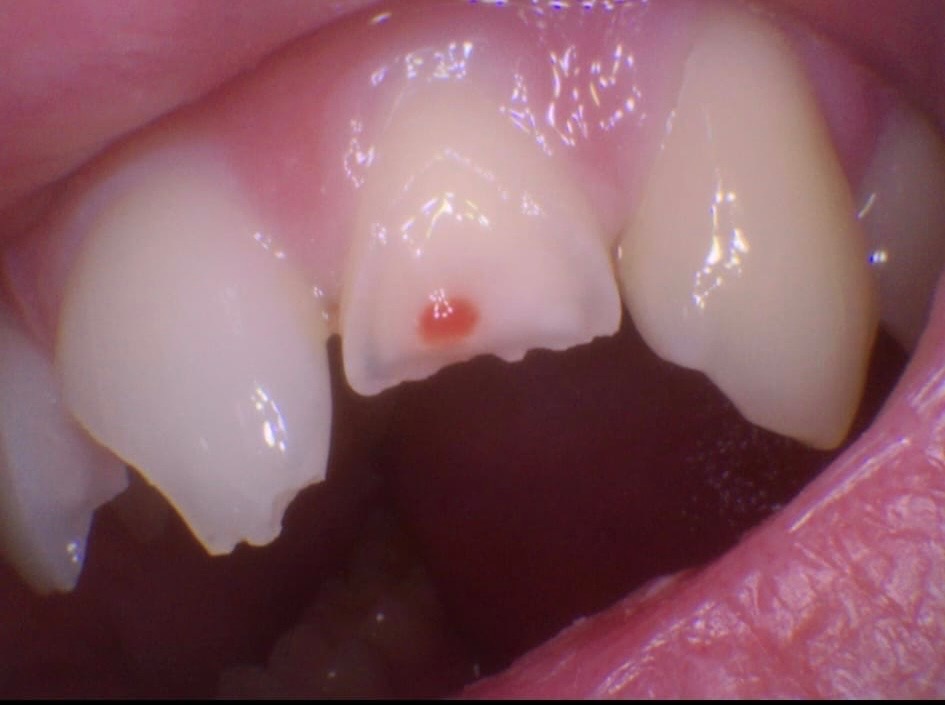

Kaiden suffered a bruised cheekbone, a black eye, concussion and extensive trauma to his teeth.

Altogether, he has six broken teeth.

Because of the exposed nerves, Kaiden is at high risk of infection and has already started a course of anti-biotics as precaution, the risk of infection gets higher the longer the nerves are exposed.

Kaiden is in constant, intense pain, and the sooner treatment can begin, the better his chances of avoiding long-term complications.